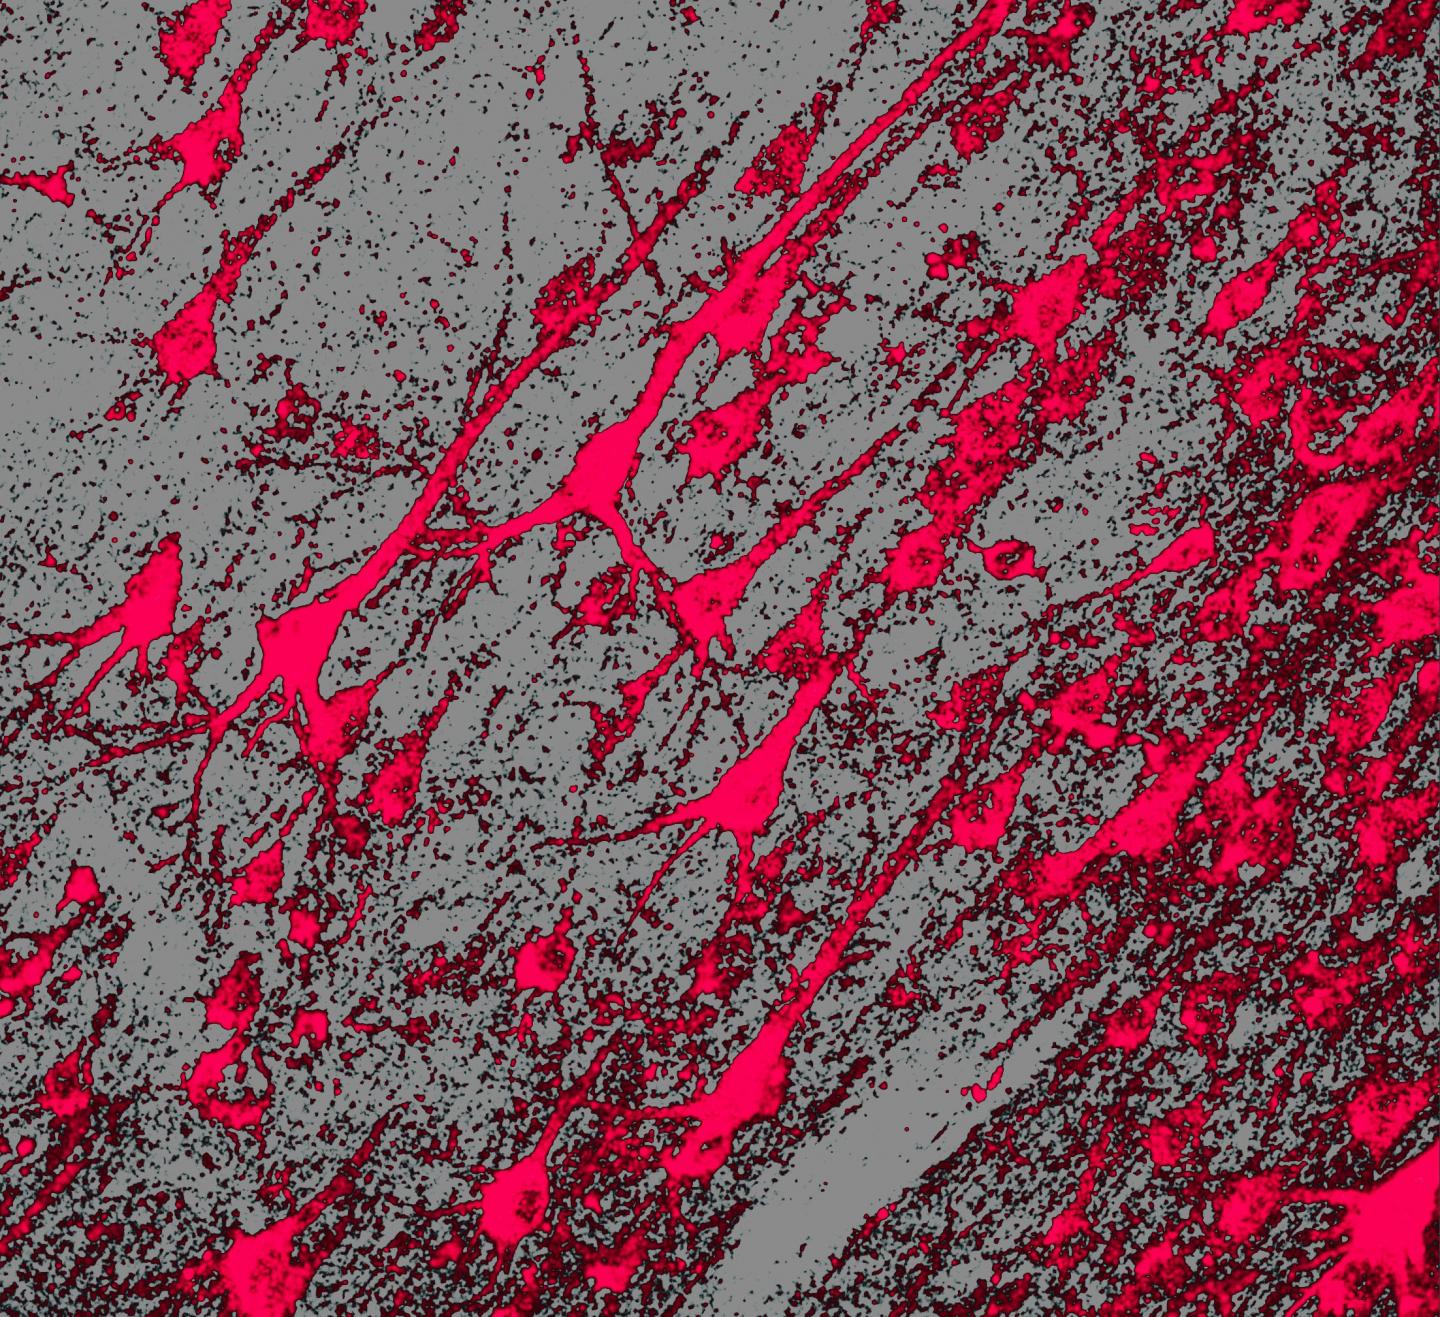

When the scientists inspected the dogs' brains, they found that the treatment reduced the damage normally caused by the disease. In comparison with untreated dogs, the treated dogs had less reactive glial cells and stored lipofuscins, fatty deposits that are hallmarks of Batten disease and similar disorders, called neuronal ceroid lipofuscinoses.

Further inspections of the dogs' brains confirmed the scientists' hypothesis about how the therapy worked. The results suggested that parenchymal cells that line the ventricles and surface of the brain took up the injected genes from the cerebrospinal fluid and made more TPP1 protein. These cells then secreted the protein that, in turn, spread throughout the brain. Initial experiments showed the importance treating the dogs with the immunosuppressant, mycophenolate mofetil, before injecting the TPP1 gene. The immunosuppressant prevented the production of antibodies that accelerated TPP1 clearance from the cerebrospinal fluid.